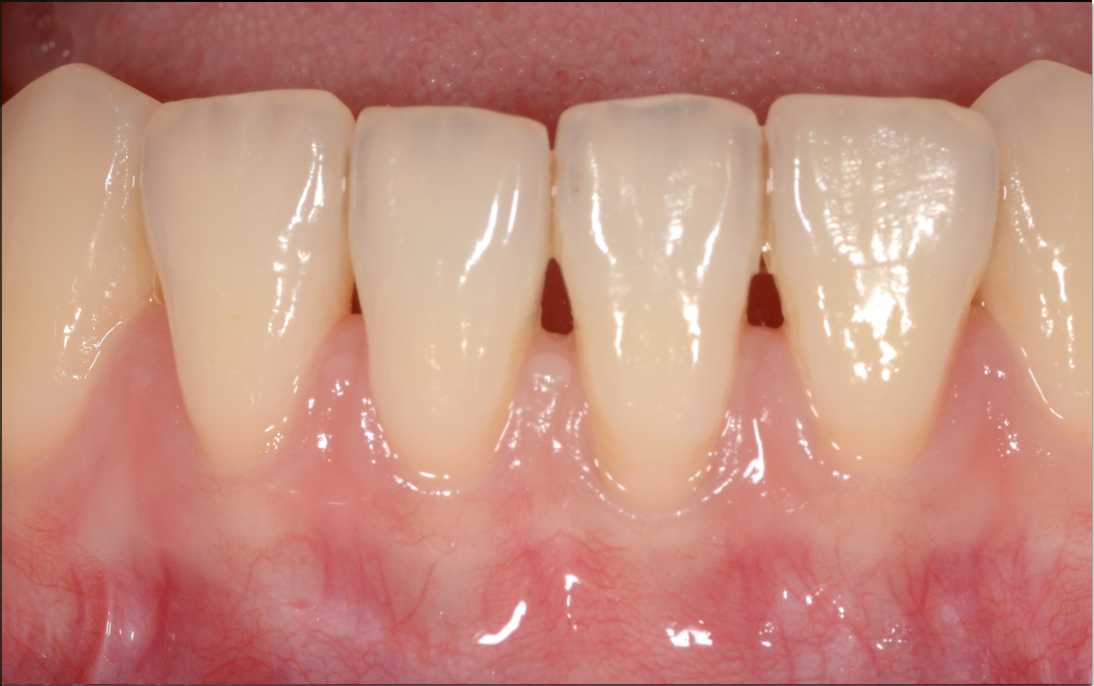

FGG(遊離歯肉移植術)で歯肉増大と歯の根元を被覆した症例

根面被覆術で歯肉退縮を改善した症例